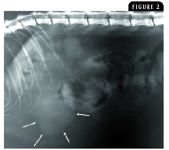

Although various primary sarcomas (leiomyosarcoma, fibrosarcoma, myxosarcoma, liposarcoma) have been reported, the most common sarcomas to affect the hepatic parenchyma are hemangiosarcoma (Figure 2) and histiocytic sarcoma.2,4 Therapy for these two sarcomas may depend on determining whether the tumor arises primarily from the liver or whether it is metastatic, which may be suggested by the size of the hepatic lesion. Surgical excision of a primary hepatic hemangiosarcoma or excisional biopsy of suspected hepatic metastases from a primary splenic hemangiosarcoma may be considered and should be followed by systemic chemotherapy with a doxorubicin-based protocol.

Figure 2. An ultrasonogram of a 9-year-old male castrated German shepherd presenting for evaluation of episodic weakness and lethargy. A large liver mass is identified, characterized by a mixed echogenic pattern with multiple hypoechoic cavitated lesions. Microscopic examination confirmed the liver tumor to be hemangiosarcoma.